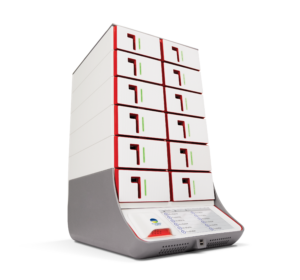

The syndromic approach combines a group of possible pathogens into one quick test. This approach takes the guesswork out of choosing which pathogens to test for. The BIOFIRE® System uses multiplex PCR technology to provide the most accurate pathogen detection on comprehensive target menus.

With fast turnaround times, BIOFIRE® Panel results help you make appropriate, optimal treatment decisions.